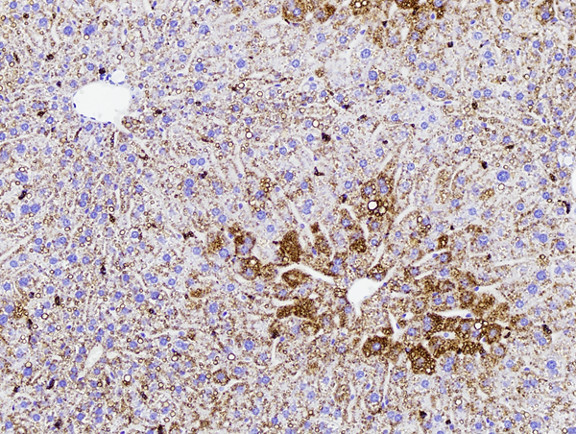

Figure 6: Histopathology for C57BL/6NTac mice placed on D09100310 diet (MASH B6NTac) or kept on chow diet (Control B6NTac) from 6 weeks of age. Animals were on diet for 27, 35 or 53 weeks. Hematoxylin and eosin (H&E) staining illustrates morphological changes including steatosis and infiltration of immune cells. Activated HSCs were identified in liver sections by using a rabbit polyclonal antibody to alpha-smooth muscle actin (a-SMA) (1:500 dilution; ab5694; Abcam, Cambridge, MA) which was detected by an anti-rabbit IgG embedded polymer with embedded horseradish peroxidase and visualized with 3,3′-diaminobenzidine (DAB) chromogen (Agilent, Carpentaria, CA). Hepatocellular lipid droplets were identified by visualization of the lipid-binding protein adipophilin known to be expressed in steatotic livers. Sections of livers were probed using a rabbit polyclonal anti-adipophilin antibody (1:200 dilution; NB110-40877, Novus Biologics, Littleton, CO) which was detected by an anti-rabbit IgG embedded polymer with embedded horseradish peroxidase and visualized with 3,3′-diaminobenzidine (DAB) chromogen (Aligent, Carpentaria, CA). Picrosirius red (PSR) staining illustrates collagen I and III fibers and is used to measure fibrosis. The same individual MASH or control animal is shown for all four stains in a particular time point. Different individual animals were used for each time point (i.e. data is not longitudinal by animal). Histopathology services provided by IDEXX BioAnalytics.